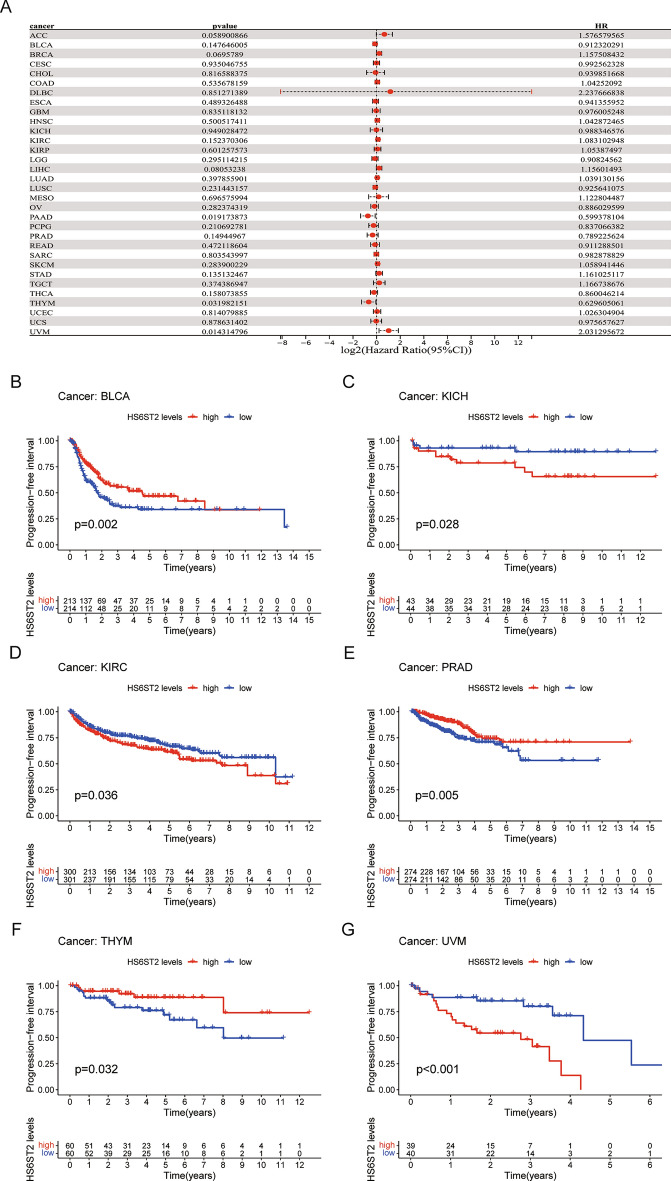

To evaluate the efficacy of radical surgery, the DFI was assessed, and this index was then used to predict the median time to recurrence. KM and Cox regression analyses showed that high HS6ST2 expression was associated with worse DFI in lung adenocarcinoma and kidney renal papillary cell carcinoma and with better DFI in bladder urothelial carcinoma (Fig. 5A–D). In addition, the correlation between PFI and HS6ST2 expression was examined to assess the responsiveness of cancers to palliative care. Cox regression analysis showed that HS6ST2 over-expression was associated with better PFI in pancreatic adenocarcinoma and thymoma but associated with poor PFI in uveal melanoma (Fig. 6A). According to the results of the KM analysis of PFI, HS6ST2 is a risk factor for patients with kidney renal clear cell carcinoma, kidney chromophobe, and uveal melanoma and a protective factor for bladder urothelial carcinoma, prostate adenocarcinoma, and thymoma (Fig. 6B–G). Our results demonstrated a significant correlation between HS6ST2 expression and outcomes in many types of cancer.